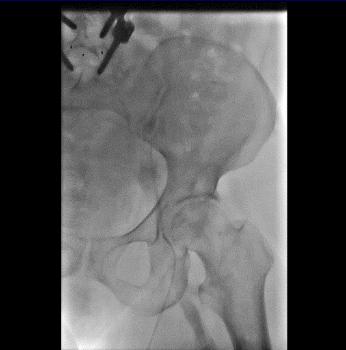

急诊造影:股总静脉、髂内外静脉大量新鲜血栓形成,见图4

图4